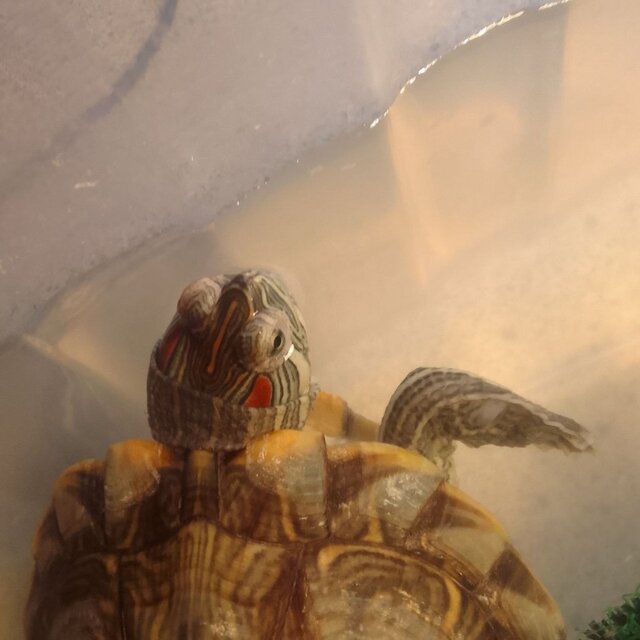

@DarthAlex 1. Уфа.26 лет мне и 11 лет крксноухой черепахе 2.Красноухая черепаха 3. Террариум. Месяц как на подоконнике стоит, раньше подсоединил комнаты стоял. И как только на окно поставили глаза отекли и не открываются. Привет рестартов на другой подоконник который не сразу в окно выходит, а на лоджию. Примерно около 70-90 литров аквариум с островком 4. нагреватель стоит для объема 60-90 литров, мощность 75. включаю лампу греющую 50W+uvb 3.0 (включаю с 8 утра и до 22-23:00) 3 недели как так работает, ранее включала раз в неделю на 2-3 часа уф лампа uvb 5.0, мощность 26вт(включаю с 8 утра и до 22-23:00) 3 недели как так работает, ранее включала раз в неделю на 2-3 часа артикул на вб на уф лампу: 332588948 Берег имеется, стеклянный фильтр имеется в аквариуме, внутренний, мощность 15вт артикул на фильтр вб: 241176284 Нагреватель воды имеется мощность 75. Артикул вб : 230910750 5. грунт имеется, Галька 8-12мм фракции 6. Температуру воды сейчас поддерживаем 27-29 градусов, температура на суше около дампы греющей 30 7. Кормила всегда только филе минтай или хек, без каких либо добавок. Кушает сейчас хорошо. Крайние два приема начала добавлять в рыбу витамины репаши витамин А 166427259 и фуд фарм кальций без д3 : 168761147 также добавила траву в аквариум крайний неделю, всю съела (фото приложу). Кормлю 1-2 раза в неделю 8. возраст 11 лет. Вес 0.41. Глаза отекли с 20.11.2025 года 9. 26 ноября 2025 года были на приеме у врача в Уфе. Рекомендация: 7-14 дней раствор рингера 10-12мл колоть (делаем уже 9 дней) , промыть глаза раствором натрий хлорид и через 20-30 минут капать по одной капле тобрамицин (3 раза в день делаем, 12-13 дней уже) также онлайн консультация другого врача покупала: посоветовала уменьшить дозу рингера до 0,8 и добавить 0,4 кальций глюконат (крайние 4 дня делаю именно так) также посоветовала Элеовит 0,2 сейчас (вчера сделала вынутримышечно) и через 2 недели повторить этот врач по снимку думает что тимпания и сказал стараться не кормить пока, а всё колоть а врач где были на оффлайн консультации предполагает пневмонию, и сказал кормить нужно с витаминами НО ЧЕРЕПАХА ХОРОШО КУШАЕТ И ОЧЕНЬ АКТИВНАЯ Также хотела добавить, что крайние 3 дня в момент укола черепаха начала писить, плохо ли это? Черепаха на левый бок всплывает, уже достаточно давно

Помогите в выборе черепахи. Авито.

Пересадил в тёплую воду в отсадник, открыла. Но опухлость века меня смущает всё равно. Такое ощущение, что есть.

1. Россия, Владимир 2. Красноухая 3. Пластиковый контейнер 47 литров, налито около половины 4.1. Лампа накаливания 60 Вт, включается на 8 часов 4.2. УФ нет 4.3. Берег есть, купленный в магазине мостик 4.4. Внутренний фильтр Wataera MY350, 5 Вт 4.5. Нагреватель установлен 5. Редкие камушки 6. 23-25 7. Раз в 3 дня, стали давать рыбку, креветки. До этого черепаха (у прошлых хозяев) питалась в основном "Чёрной львинкой". ест и как часто? 8. Около полутора лет, панцирь 12 см, вес не знаю. Третий день наблюдаю, что черепаха не открывает левый глаз такое ощущение, что веко опухлое. 9. Нет.